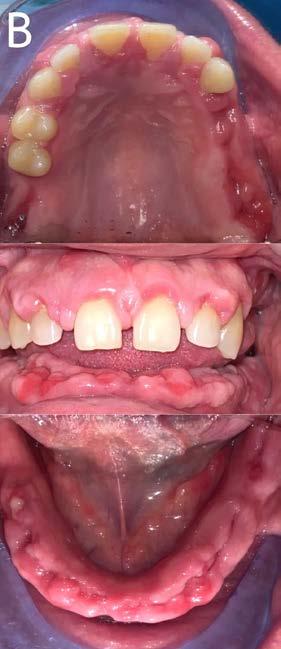

Figura 3. Fotografías intraorales.

hace 8 años por lo que toma 30 mg de nifedipino cada 12 horas, amlodipino 5 mg cada 24 horas, telmisartan 40 mg cada 12 horas y metropolol 100 mg cada 12 horas, además comenta padecer diabetes mellitus tipo II desde hace 7 años por lo que también toma 50 mg de metformina cada 12 horas y dapagliflozina 10 mg cada 24 horas. Clínicamente se observó una encía roja y sangrante, profundos sondeos, una notable hiperplasia gingival, depósitos de cálculo y movilidad dental grado III en todos los órganos dentarios a excepción del segundo premolar superior derecho al canino superior izquierdo, quienes presentaban una movilidad grado II. Radiográficamente se encontró una pérdida de inserción radiográfica avanzada generalizada

en la arcada inferior, y grupos molares de ambos cuadrantes superiores (Figura 1), los únicos órganos dentarios con posibilidad de preservación en boca a través de terapia periodontal se encontraron en el sector anterior de la arcada superior anteriormente mencionados con movilidad grado II

(Figura 2). Por lo que se diagnostica con periodontitis generalizada, estado IV, grado C (Figura 3).